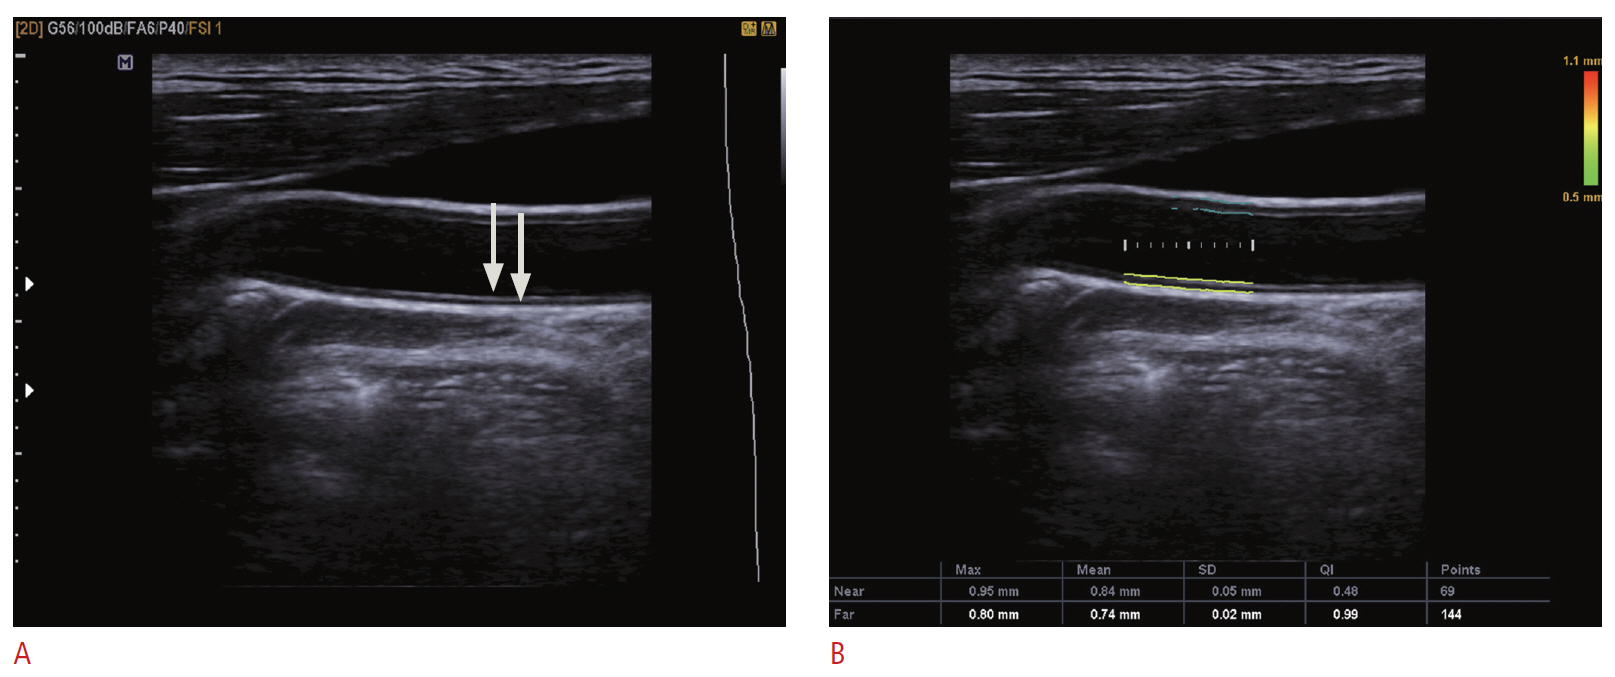

Carotid Doppler ultrasonography is a popular tool for evaluating atherosclerosis of the carotid artery. Its two-dimensional gray scale can be used for measuring the intima-media thickness, which is very good biomarker for atherosclerosis and can aid in plaque characterization. The plaque morphology is related to the risk of stroke. The ulceration of plaque is also known as one of the strong predictors of future embolic event risk. Color Doppler ultrasonography and pulse Doppler ultrasonography have been used for detecting carotid artery stenosis. Doppler ultrasonography has unique physical properties. The operator should be familiar with the physics and other parameters of Doppler ultrasonography to perform optimal Doppler ultrasonography studies.